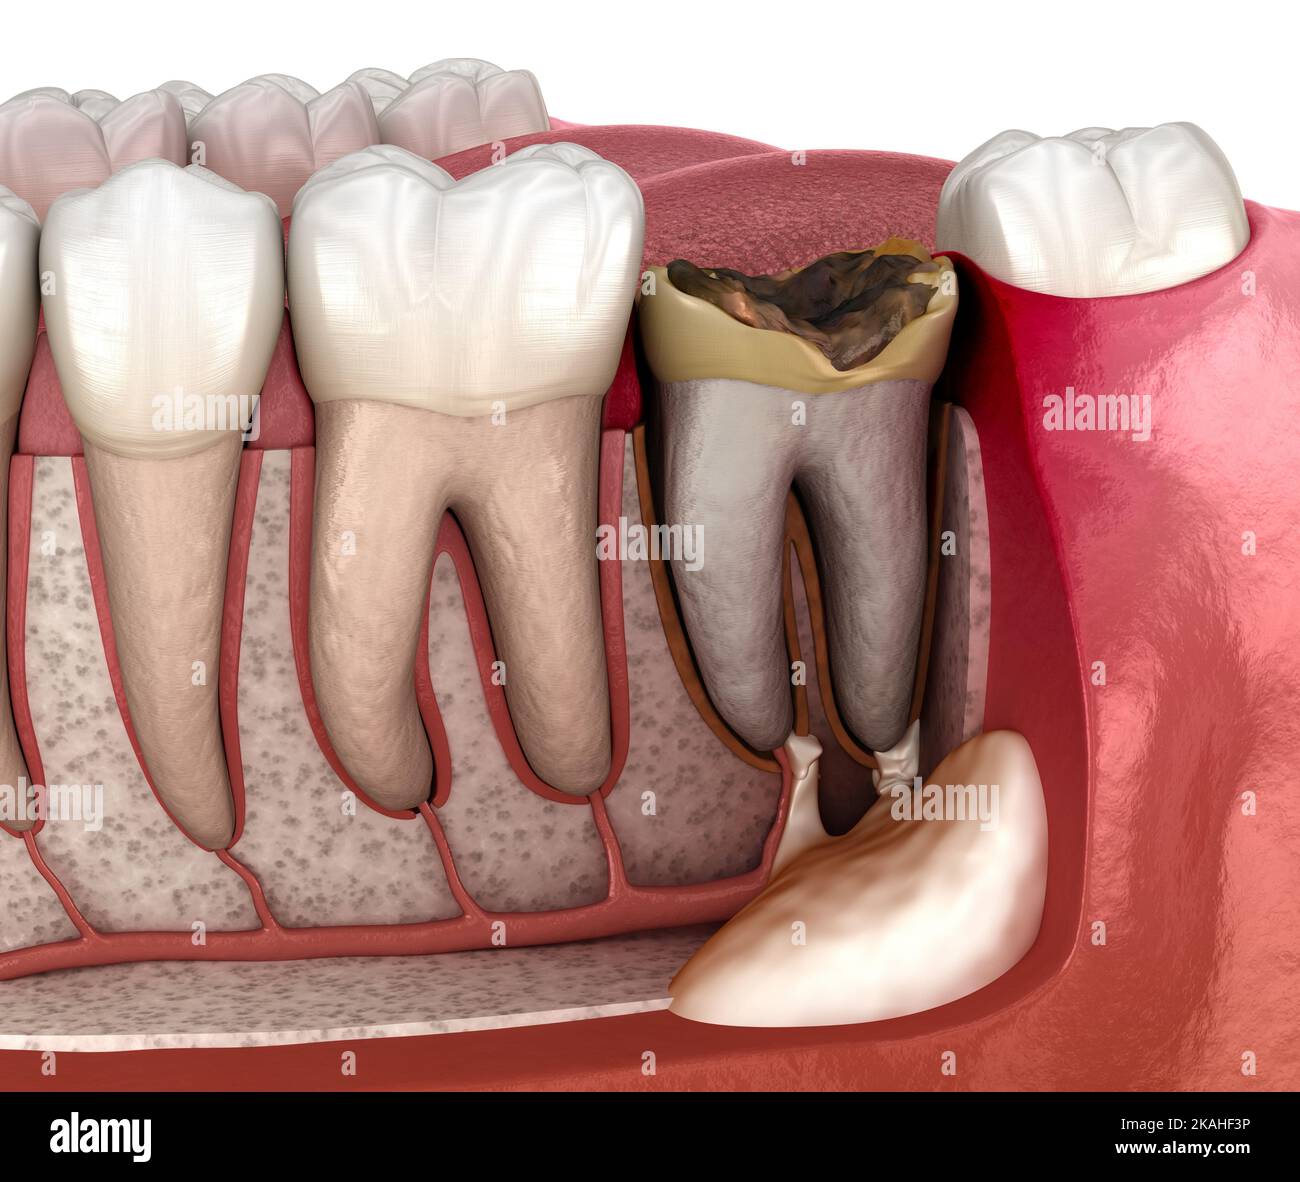

From www.dreamstime.com

Periostitis Tooth Lump on Gum Above Tooth. Medically Accurate Dental Periostitis Jaw What are the histologic and. — a total of 156 patients with chronic osteomyelitis, proliferative periostitis (garre osteomyelitis),. — garre’s osteomyelitis of the jaw refers to a particular type of pathological change and clinical manifestation of chronic marginal. — chronic osteomyelitis with proliferative periostitis is a rare form of osteomyelitis that is characterised by new. —. Periostitis Jaw.